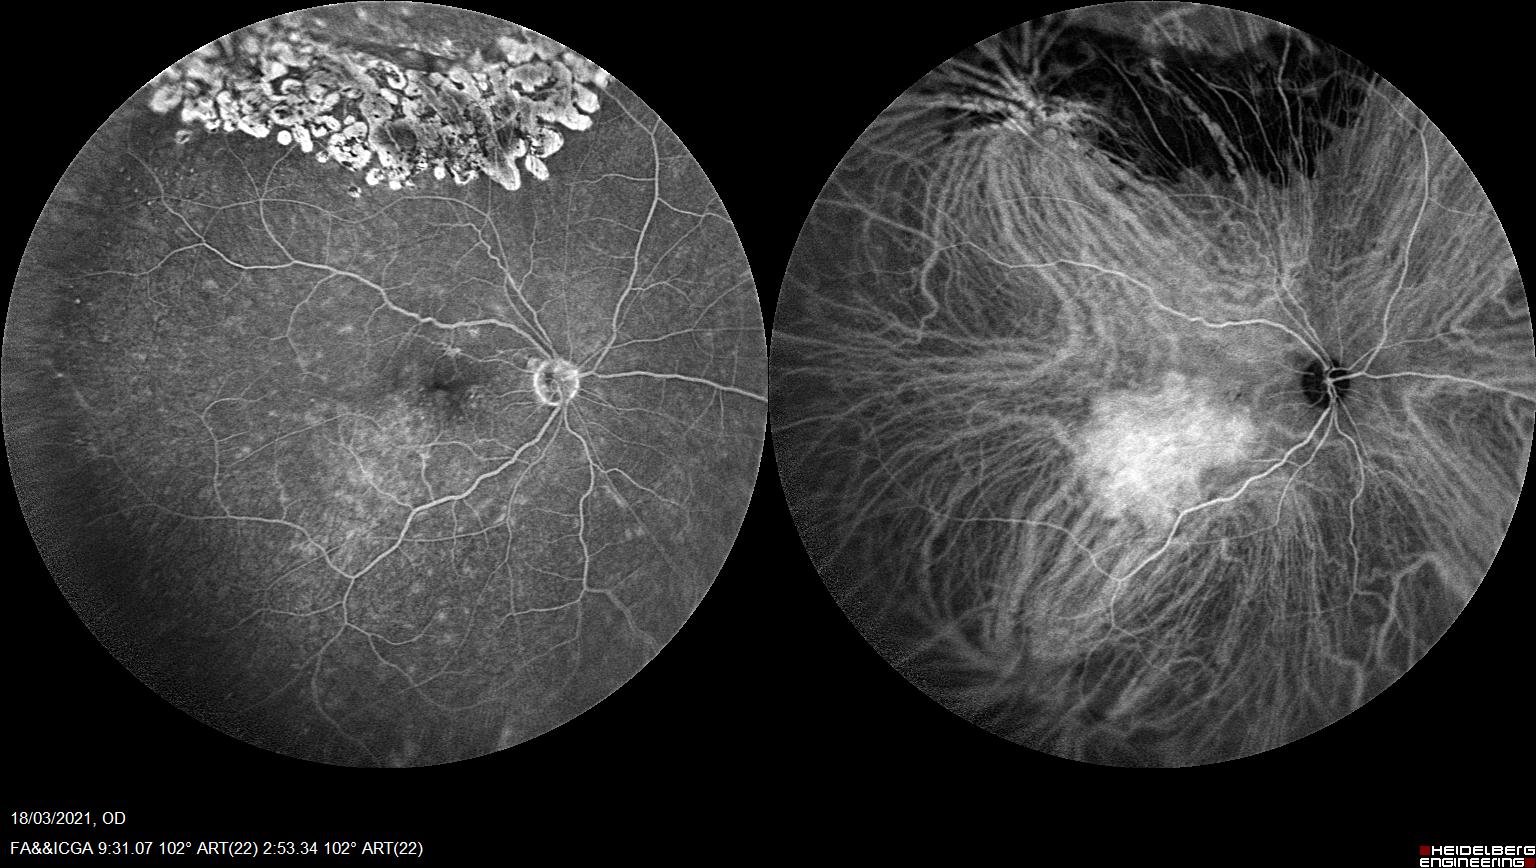

Una de las herramientas más útiles para su diagnóstico es la angiografía con verde de indocianina.

En la ICV podemos apreciar una hipercianescencia precoz con una iso/hipocianescencia tardía que refleja el alto flujo vascular y capacidad de lavado que presentan estos tumores vasculares a diferencia de otros funduscopicamente similares.